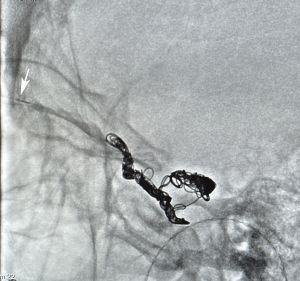

6. The guidewire and microcatheter is introduced through the catheter into the SOV under fluoroscopic guidance.

7. The cavernous sinus is successfully accessed, the guidewire is removed and the embolization device (balloon, coil, etc.) is positioned through the microcatheter. The neuro-interventional radiologist performs angiography and then the embolization. Final angiography is done to confirm cessation of flow through the fistula.